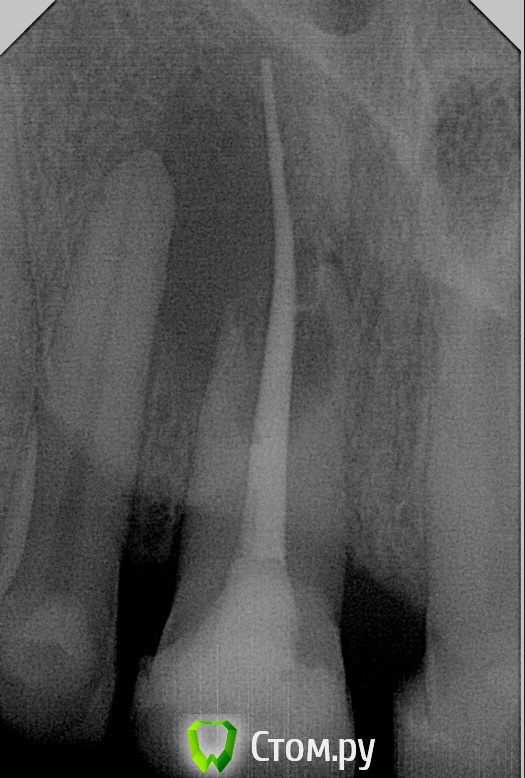

SanderS Опубликовано 17 ноября, 2014 Поделиться Опубликовано 17 ноября, 2014 Новую тему решил не создавать, добавлю в эту. Пациент - жалобы на припухлость губы, болит зуб - 3 года назад делали реставрации фронта 1.2-2.2. 1.1 на холод не реагирует...делаю снимок - . Отправил на КТ - вестибулярная и небная кортикалка отсутствует(скрины КТ могу сделать вечером). Когда можно будет ставить имплантат и чем обеспечить хорошее заживление с восстановлением костной ткани? Какие могут быть причины ? У пациента дистальная окклюзия. Травмы отрицает. Ссылка на комментарий

SanderS Опубликовано 18 ноября, 2014 Поделиться Опубликовано 18 ноября, 2014 Соседи витальные, в общем шеф удалил.Судя по всему термофил, сказал что возможно лечили около 10 лет назад. Ссылка на комментарий